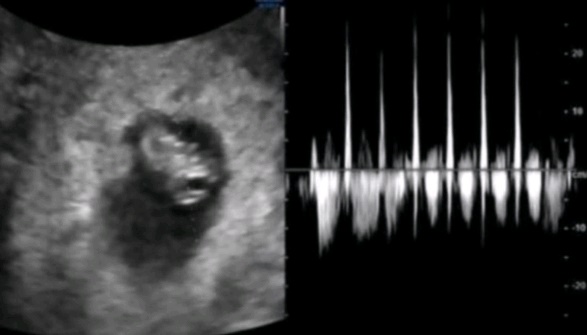

임신14주 증상/ 배가 점점 나와요! 성별확인

안녕하세요 쪼꼬미에요 :) 4월에 들어섰는데 날씨는 왜이렇게 추운거죠? 이게 거짓말인거죠?ㅜㅜ 오늘 만우...